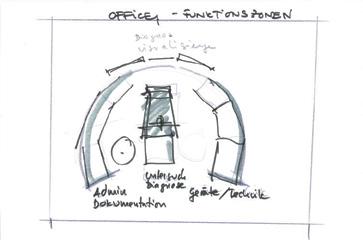

Derivate dintr-o linie lungă de modele, unităţile de tratament sunt proiectate ergonomic pentru a simplifica procedurile ENT OPD, pentru a îmbunătăţi considerabil eficienţa și a reduce oboseala utilizatorilor în camera de consultanţă / tratament ORL.

FUTURENT® III

MICRONOMIC® III

Mioveni-Argeș • Tel: +40 348 451 038 • E-mail: office@primeramed.ro • Web: www.primeramed.ro DISTRIBUITOR EXCLUSIV